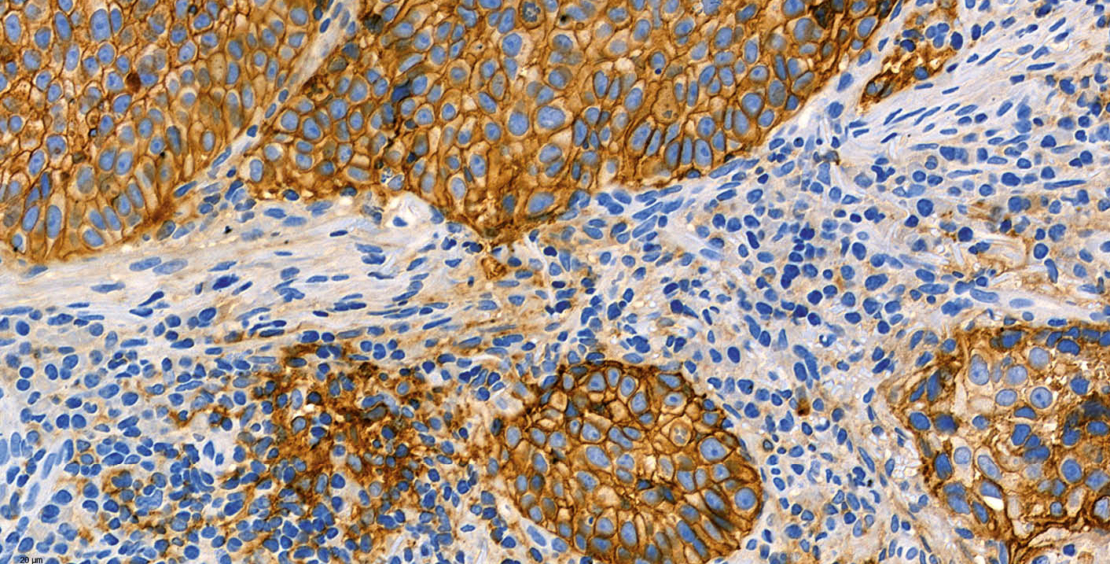

Der PD-L1 Status eines Tumors wird mittels immunhistochemischer Expressionsanalyse des PD-L1 Proteins ermittelt (Abb. 1). In klinischen Studien wurden vor allem vier kommerzielle PD-L1 Testkits verwendet: PD-L1 IHC 28-8 pharmDx (28-8), PD-L1 IHC 22C3 pharmDx (22C3), Ventana PD-L1 SP142 (SP142), und Ventana PD-L1 SP263 (SP263). Bei diesen Testkits handelt es sich um geschlossene Reagenzien-Systeme, die nur auf den Geräteplattformen der entsprechenden Hersteller eingesetzt werden können. Die in den Testkits verwendeten Primärantikörper (22C3, 28-8, SP142, SP263) sind allerdings auch als Einzelreagenzien verfügbar, so dass Pathologie-Institute mit diesen auch sog. Labor-entwickelte Tests (LDT) etablieren können. Weitere, häufig deutlich kostengünstigere PD-L1 Primärantiköper (u.a. E1L3N) stehen zur Verfügung, die bisher jedoch nur in wenigen klinischen Studien evaluiert wurden. Technisch kann eine PD-L1 Immunfärbung an Gewebeproben und zytologischem Probenmaterial durchgeführt werden. Bei jedem Färbedurchgang sollte ein positives Kontrollgewebe (bevorzugt Tonsillengewebe) als On-slide-Kontrolle zur internen Qualitätskontrolle mitgeführt werden. Für die Auswertung muss das Probenmaterial eine ausreichende Anzahl von Tumorzellen und/oder Immunzellen enthalten.

Der Tumor Proportion Score (TPS) entspricht dem relativen (prozentualen) Anteil der Tumorzellen mit PD-L1 Positivität. Als PD-L1 positiv werden Tumorzellen mit einer kompletten oder inkompletten PD-L1 Färbung der Tumorzellmembran beurteilt, unabhängig von der Färbeintensität.

Der Combined Positive Score (CPS) berücksichtigt die PD-L1 Expression von Tumorzellen und tumorassoziierten Immunzellen (Makrophagen, Lymphozyten, dendritische Zellen). Zur Ermittlung des CPS wird in mehreren Gesichtsfeldern (bei 200-facher Vergrösserung) die Zahl der positiven Tumorzellen und Immunzellen bestimmt. Bei Tumorzellen gilt eine membranäre Anfärbung unabhängig von der Intensität als positiv, bei Immunzellen nur eine zytoplasmatische Anfärbung. Die Summe der PD-L1 positiven Zellen wird durch die Anzahl der Tumorzellen in den Gesichtsfeldern dividiert und der Quotient mit 100 multipliziert. Es entsteht ein dimensionsloser Wert, der dem CPS entspricht.